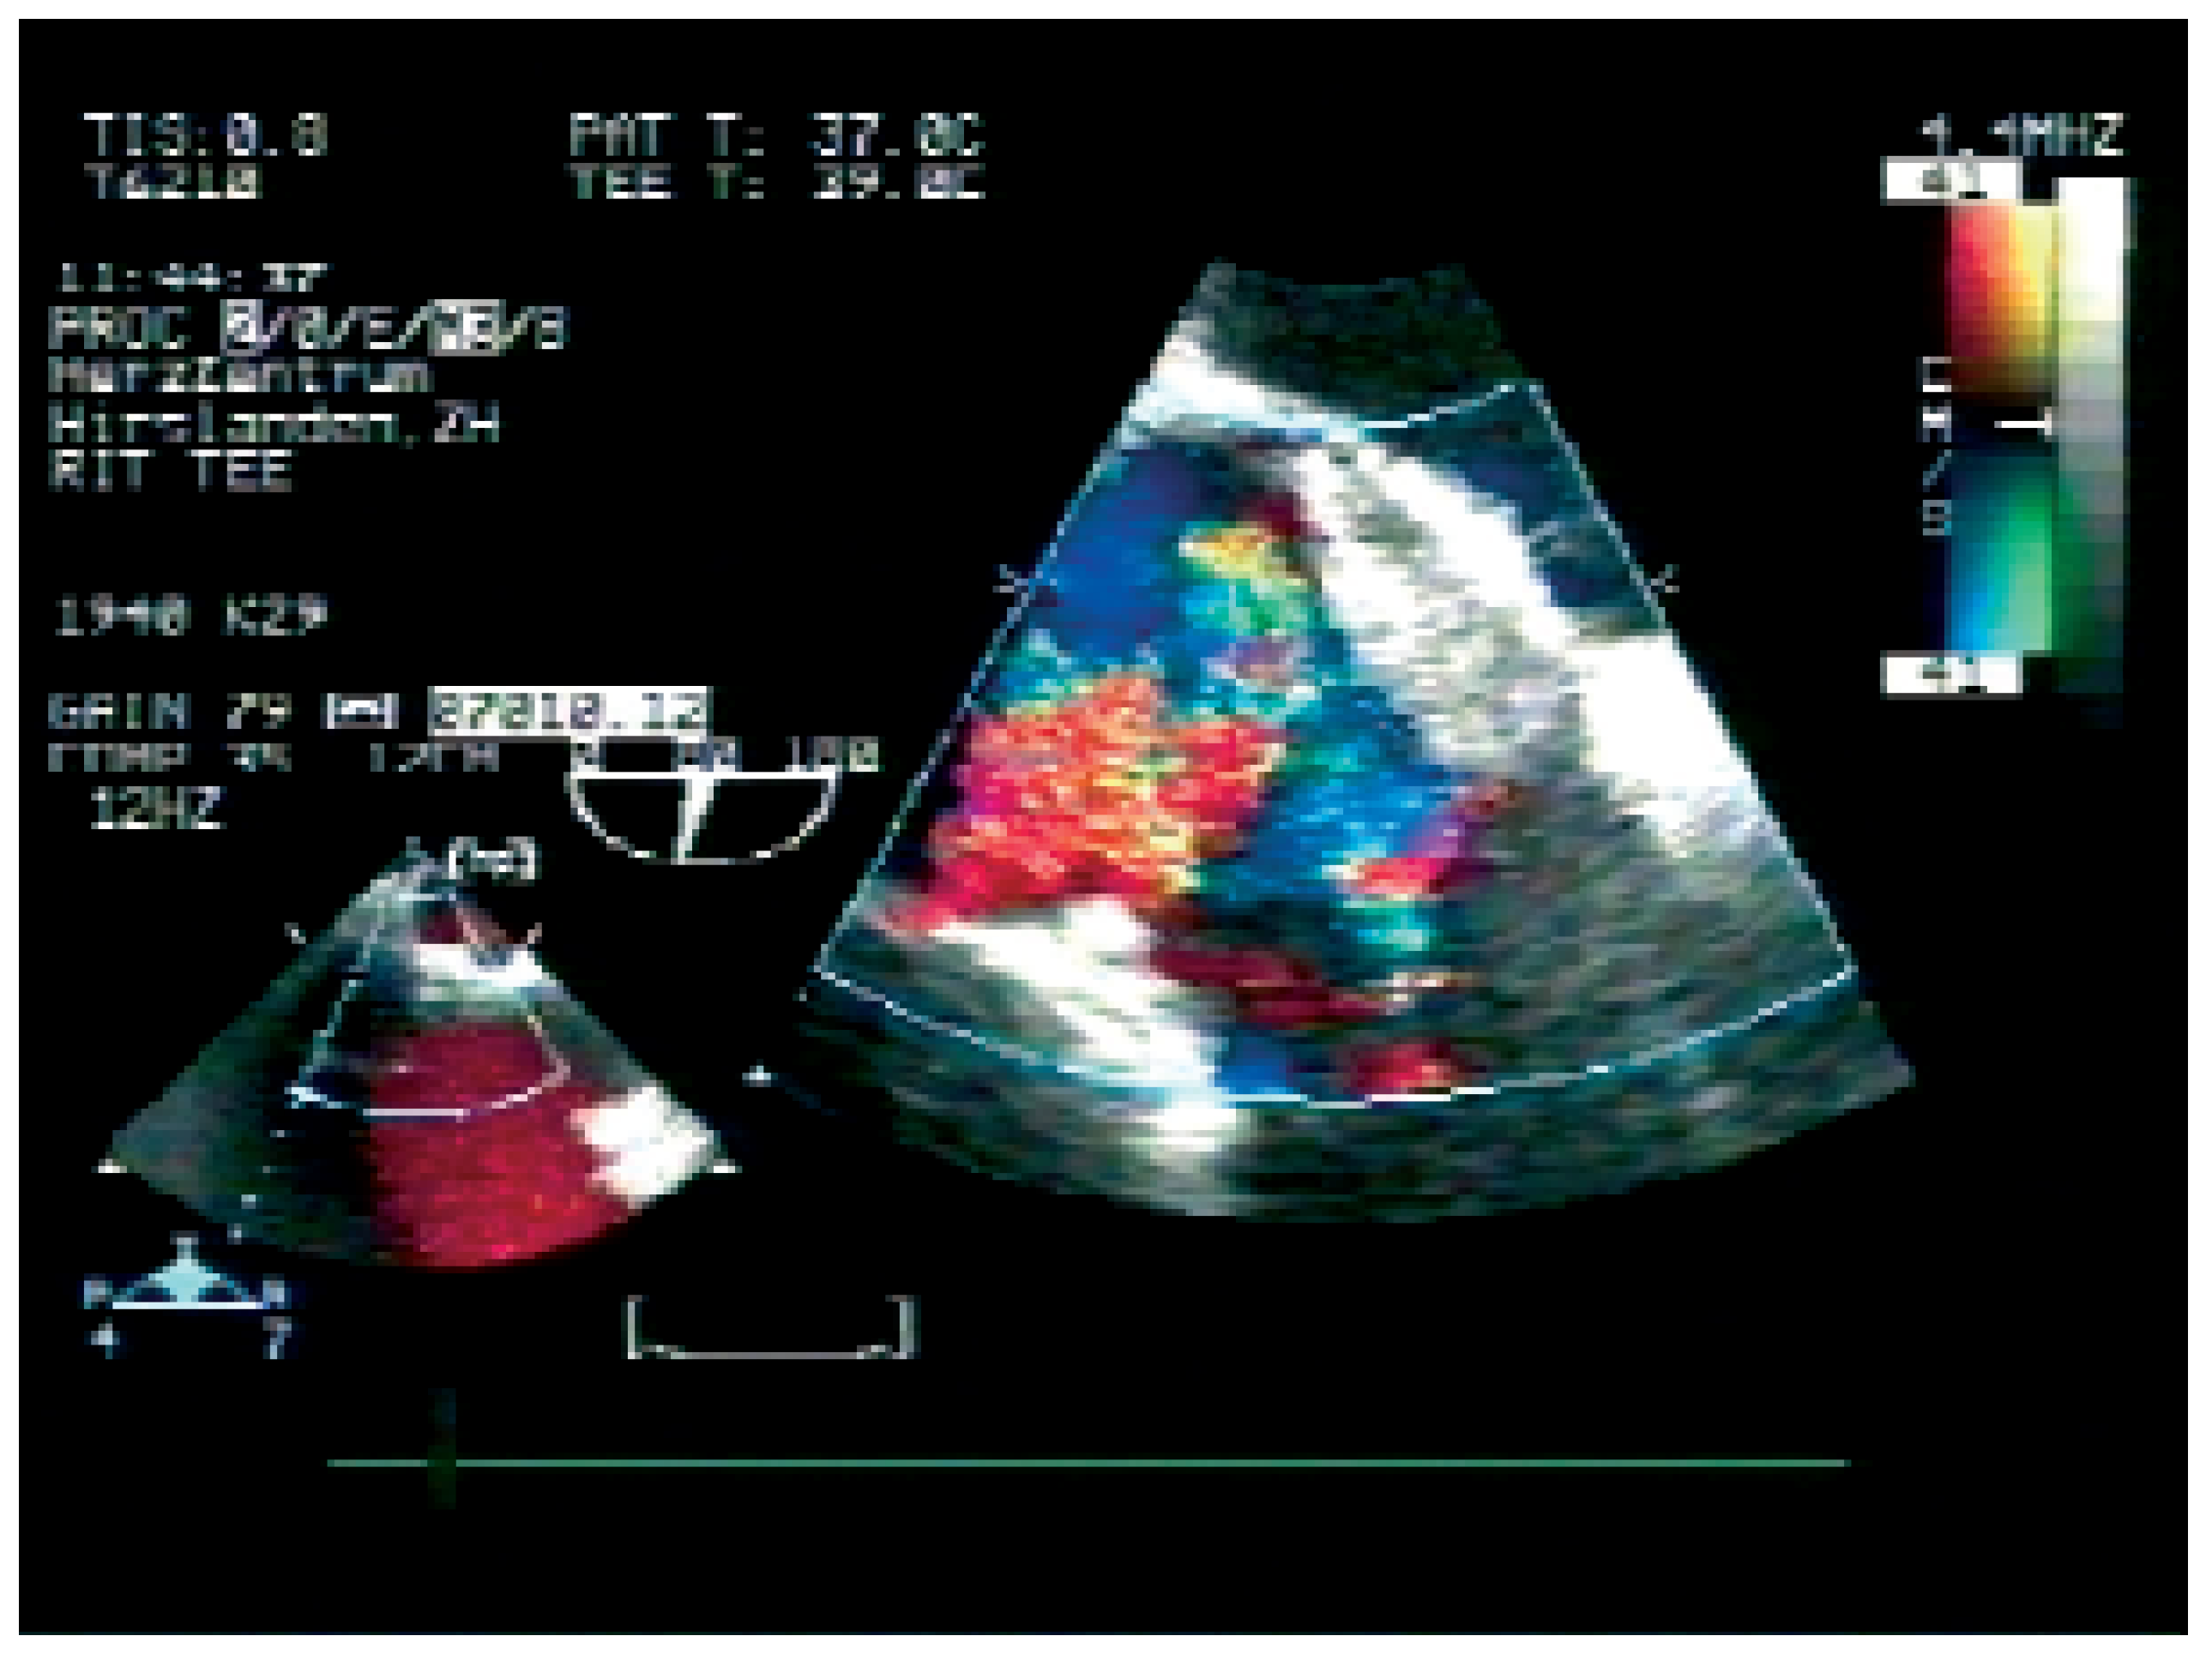

Abbildung 3. Transösophageale Kontrolluntersuchung 6 Monate nach OFO-Verschluss ohne Rest-Shunt mittels Farbdoppler oder Bubble-Injektion, nach Husten und Pressen (es handelt sich nicht um den gleichen Patienten wie in Abbildung 1 und 2).